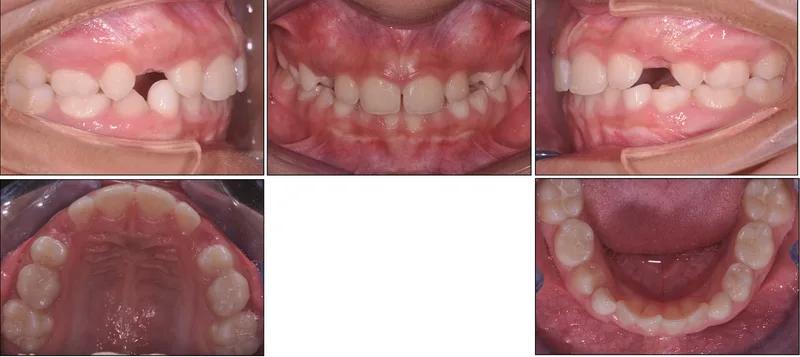

Il palato stretto è una condizione molto frequente nei bambini al giorno d'oggi e va trattato prima possibile. Spesso al palato stretto è associata una mancanza di spazio per gli incisivi laterali superiori.

I pazienti che hanno un palato stretto possono anche avere problemi di respirazione durante la notte. Spesso questa condizione richiede il trattamento con l'espansore palatale o disgiuntore, un'apparecchiatura fissa che agisce sulla sutura palatina.

Un palato stretto causa spesso affollamento dentale e mancanza di spazio per gli incisivi laterali superiori. La correzione precoce può evitare estrazioni future.